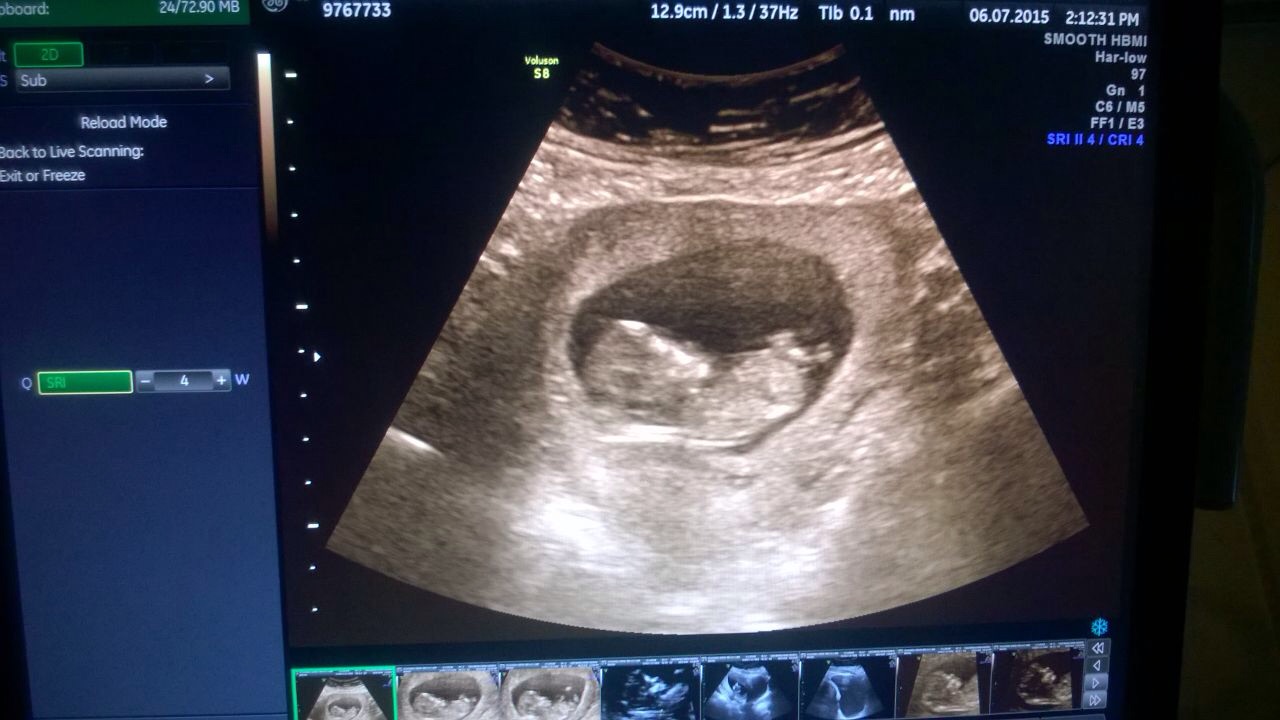

• Had my ultrasound today and it was completely beautiful, despite baby being sleepy there doing great!

Thank you for all of your words of support and the best of luck to you all! Xxxx

• My beautiful baby xxxx